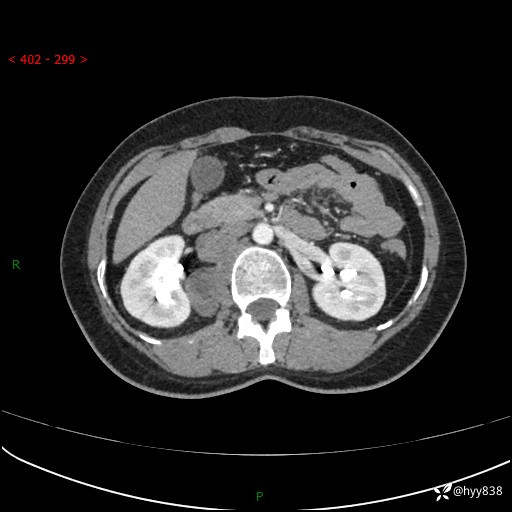

现在都流行跨界,病变也不例外,从腹膜后长到胸腔了---结果公布~

主诉:体检发现右侧腹膜后肿物1天

简要病史:患者于1天前因体检发现右旁肾占位,无肉眼血尿,无畏寒发热,无咳嗽咳痰,无腰腹部疼痛不适,无尿频尿急症状,起病来,患者未行特殊治疗,为求进一步诊治,门诊以"右侧腹膜后肿物"收治入院。 发病来患者精神、饮食、睡眠良好,小便如上,大便正常,体重无明显变化。

临床诊断:腹膜后肿物

上腹部CT增强(动脉期+实质期)(外院平扫)